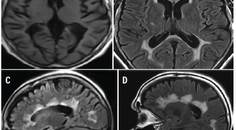

Commercially available software can automatically calculate volumes of hippocampi and other structures, but these packages have not been widely implemented outside major academic institutions. MRI-based visual rating scales using routine clinical sequences, such as entorhinal cortex atrophy (ERICA) and medial temporal atrophy (MTA) scales (Figure 1), are sometimes used as auxiliary biomarkers of neurodegeneration in AD.1 By assessing several medial temporal lobe structures, the MTA scale has been demonstrated to provide good discrimination between individuals with AD and healthy controls in a memory clinic.2 The ERICA score rates the volumes of the entorhinal and parahippocampal gyrus. Another rating tool, the Fazekas scale, rates the severity of white matter disease, which is commonly seen in individuals with vascular cognitive impairment or other clinical scenarios.

Figure 1. Medial temporal atrophy (MTA) rating scale. Cropped T1-weighted coronal images of the right medial temporal lobes demonstrate progressive hippocampal atrophy and corresponding enlargement of the adjacent portion of the right lateral ventricle. From Flodin FF, Haller S, Poom L, Fällmar D. Congruency between publicly available pictorial displays of medial temporal lobe atrophy. Eur Radiol. 2025;35(10):5944-5953.1 Used with permission (http://creativecommons.org/licenses/by/4.0).